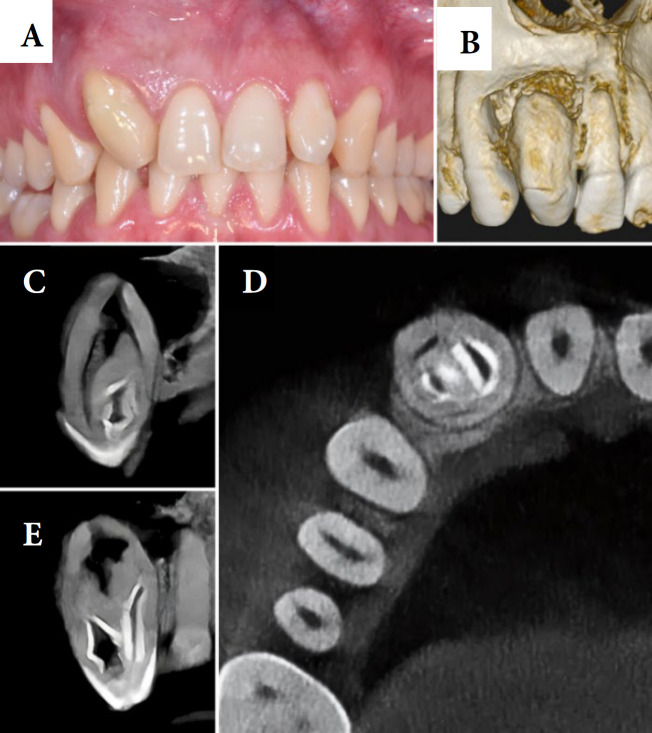

牙凹是一种发育畸形,是由牙釉质器官在组织钙化之前内陷到牙乳头内部区域引起的。本报告的目的是讨论一个临床病例的根管治疗#12牙,使用生物陶瓷封口剂。口腔外检查显示解剖不典型,活力和敲击试验阴性,触诊试验阳性。邻近牙龈黏膜水肿。根据临床和断层检查结果,诊断为牙髓坏死合并慢性根尖周脓肿和Oehlers型牙槽内陷。在第一阶段,在手术显微镜(OM)和超声金刚石尖端的帮助下,使用球形钻头进行手术。找到了四条管道,并对其进行了部分清理和药物治疗。在第二阶段,进行了牙镜测量和镍钛器械化学机械制备。冲洗液为2.5%次氯酸钠。用氢氧化钙糊剂填充根管,暂时封闭根管腔。在第三次治疗中,超声冲洗进行最后的清洗,使用经典的单锥技术用Bio-C密封剂填充根管。在6个月的随访中,牙齿无症状,x线摄影显示明显的骨修复。结论采用断层扫描、手术显微镜、超声冲洗、生物陶瓷封口剂等流量较大的材料,提高了临床病例的成功率。

Dens invaginatus is a developmental malformation that is caused by the invagination of the enamel organ into the internal region of the dental papilla before tissue calcification. The aim of the present report is to discuss a clinical case of endodontic treatment of tooth #12, using bioceramic sealer. The extraoral examination revealed atypical anatomy, while vitality and percussion tests were negative, palpation test was positive. Edema was observed in the adjacent gingival mucosa. Based on clinical and tomographic findings, the diagnosis was pulp necrosis with chronic periapical abscess and Oehlers' type II dens invaginatus. In the first session, access surgery was performed with spherical drills with the aid of an operating microscope (OM) and an ultrasonic diamond tip. Four canals were located, and they were partially debrided and medicated. In the second session, odontometry and chemical-mechanical preparation with nickel-titanium instruments were performed. The irrigation solution was 2.5% sodium hypochlorite. The root canals were filled with calcium hydroxide paste and the chamber was temporarily sealed. During the third session, ultrasonic irrigation was applied for final washing and the root canals were filled with Bio-C sealer using the classic single-cone technique. At 6-month follow-up, the tooth was asymptomatic and the radiography revealed significant bone repair. It was concluded that tomography, operating microscope, ultrasonic irrigation, and materials with greater flow, such as bioceramic sealers, enhanced the clinical success of the clinical case.